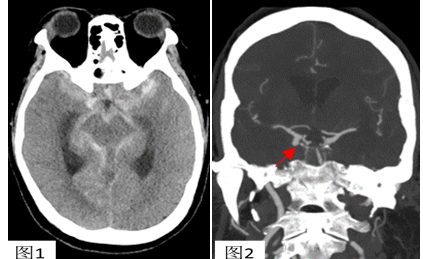

头颅CT显示左侧基底池及侧裂血量较对侧多;头CTA断层可清楚显示右侧后交通段动脉瘤